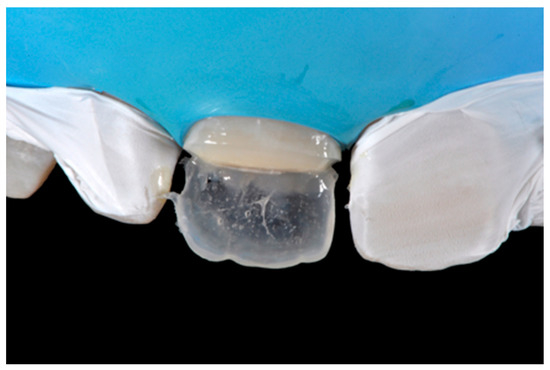

2.1.3. Completion of the Layering Procedure, Finishing and Polishing

A single shade of dentin (Clearfil Majesty ES-2, A1D, Kuraray Noritake Dental, Tokyo, Japan) was then applied placing separate increments (Figure 10 and Figure 11) to build the dentinal body, leaving space for incisal translucencies. The translucent shade (Clearfil Majesty ES-2, A1E, Kuraray Noritake Dental, Tokyo, Japan) was then applied to complete the restoration (Figure 12).

Figure 12.

Enamel layer applied. Reprinted from Restauri diretti nei settori anteriori, G. Paolone, S. Scolavino, © 2021, with permission from Quintessence Publishing Italy.